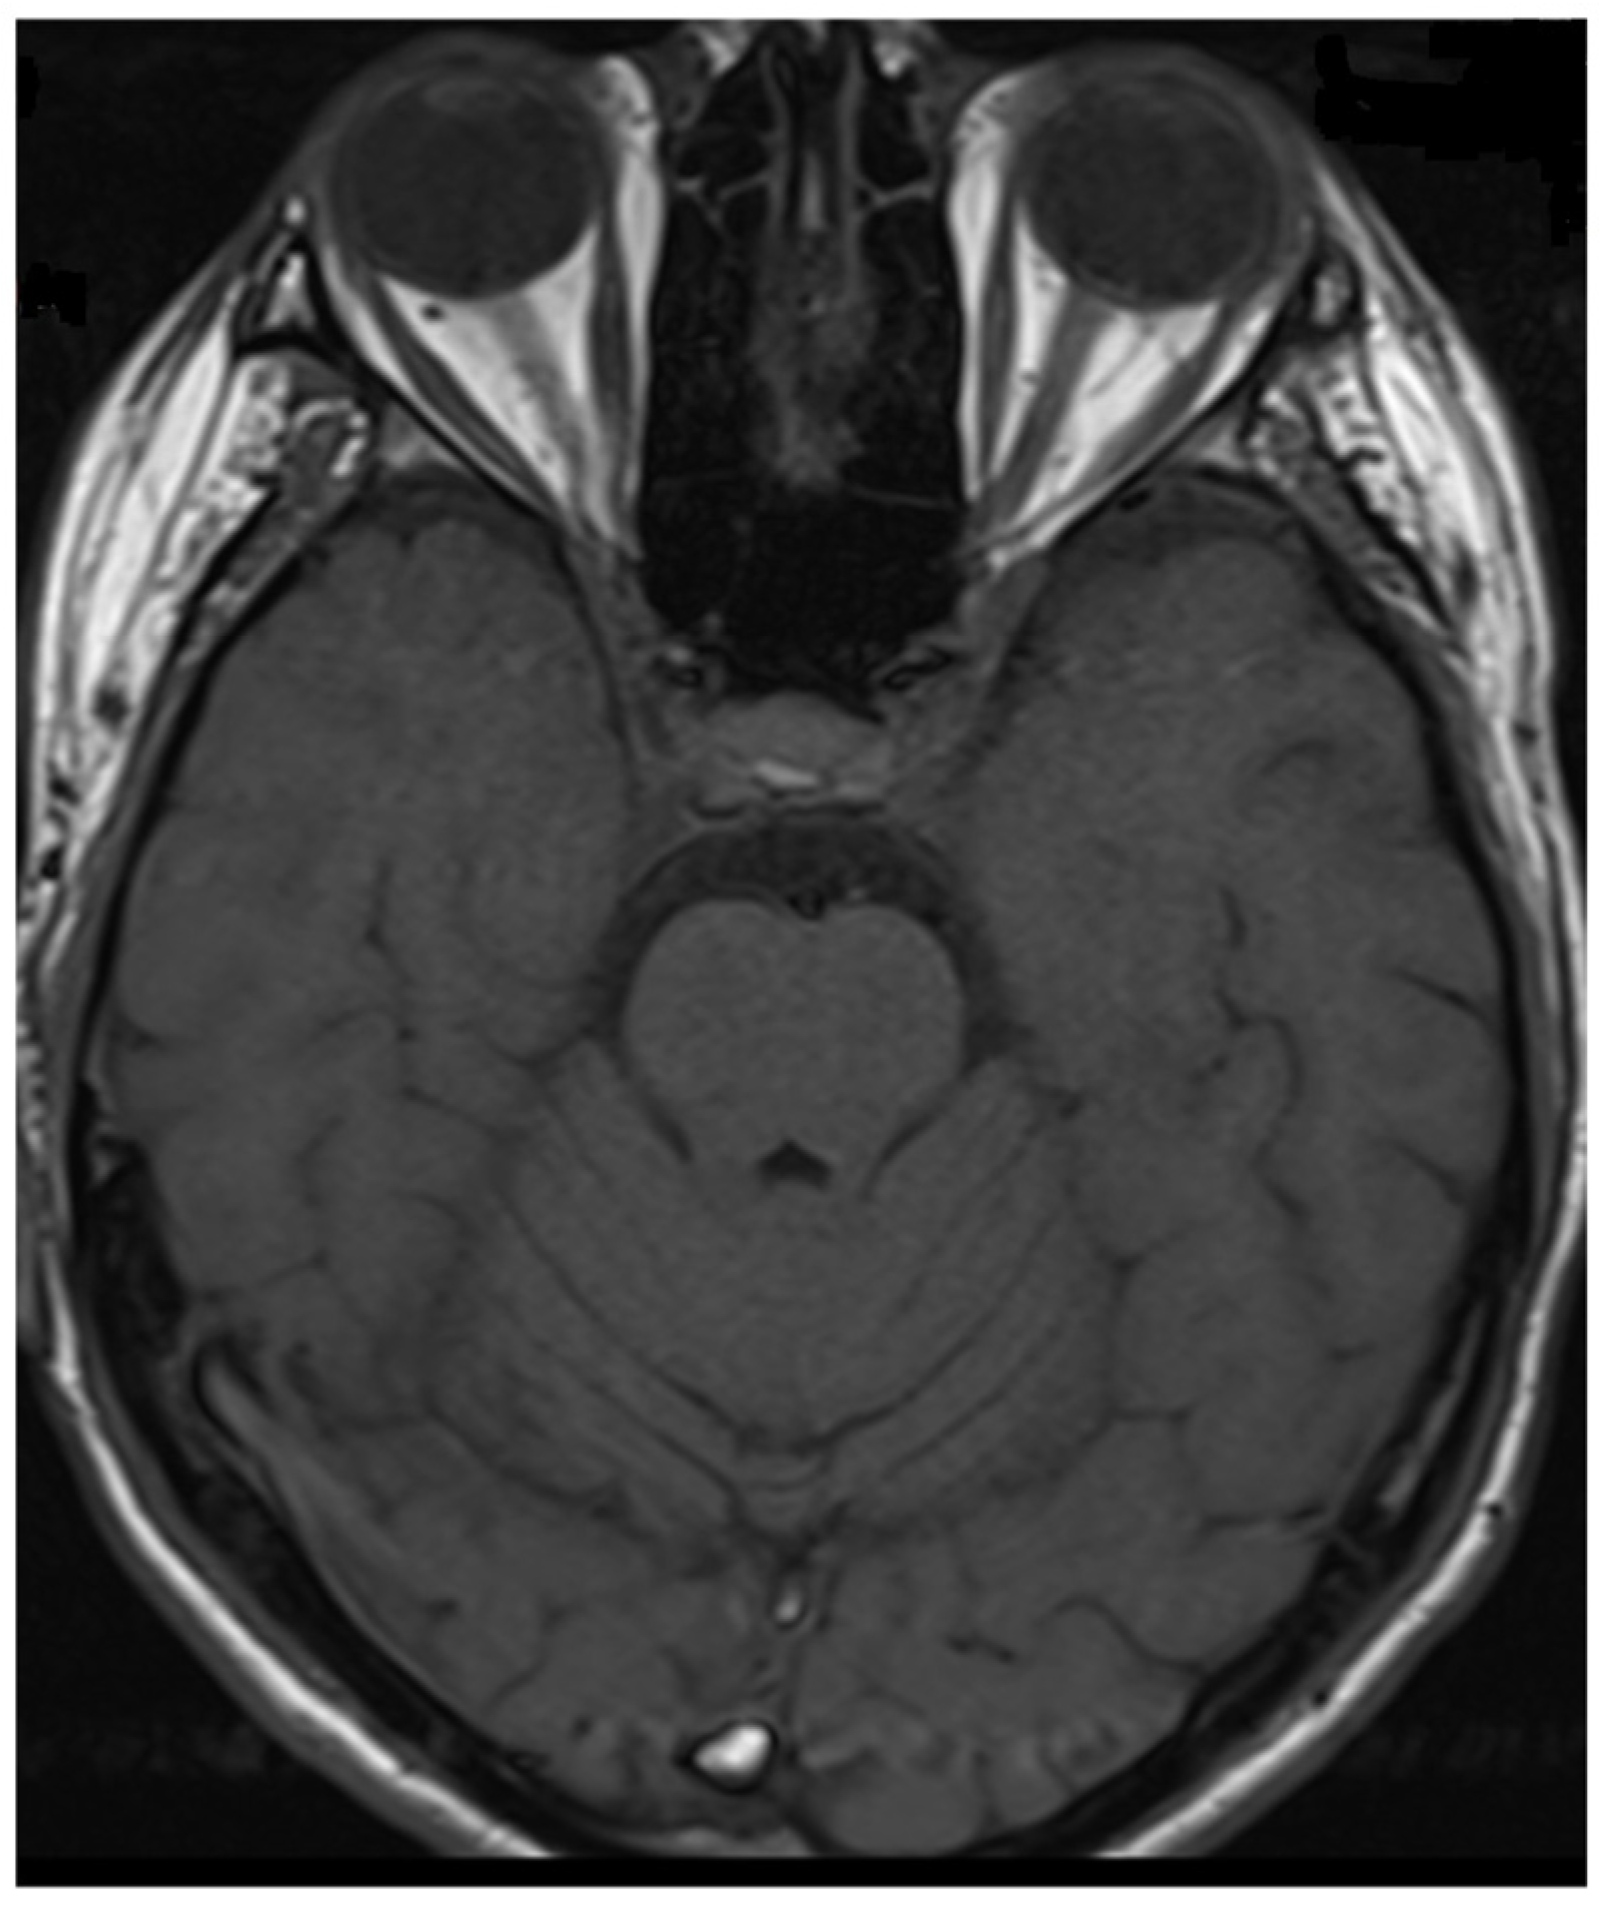

Figure 3.

Transverse FLAIR brain magnetic resonance image showing numerous foci of increased signal between the basal nuclei (December 2021).

During hospitalization in the neurology ward, Holter EEG was performed in which seizure episodes corresponded to changes in the recording. Interictal EEG showed rapid activity followed by slow theta waves and several sharp and slow wave complexes (Figure 1 and Figure 2). Topiramate was added to valproic acid at a target dose of 2 mg/kg of body weight. Gradual seizure relief was observed in the following weeks, and there were no other neurological manifestations for another nine months. After that time, in December 2021, the patient was admitted to the pediatric ward due to impaired consciousness and persistent vomiting, followed by paresis of the lower limbs. A brain MRI was performed, which showed “T2/FLAIR images reveal poorly defined areas of increased signal in the brain’s white matter, both above and below the tentorium, as well as in the periventricular and subcortical regions. These areas correspond to low signal regions in T1 images. The largest change area measures 19 × 14 mm and is located in the right middle cerebellar peduncle, which merges with changes observed in the pons. Additionally, there is a lesion in the right thalamus, measuring 10 × 24 mm, along with numerous scattered foci in the corona radiata and between the basal nuclei. Overall, the imaging findings primarily suggest acute disseminated encephalomyelitis (ADEM)” (Figure 3 and Figure 4). Cerebrospinal fluid examination revealed oligoclonal bands and an elevated protein level of 118.5 mg/dL (reference range: 15.0–45.0 mg/dL) and a slightly elevated leukocyte level of 29/mm3 (lymphocytes 72.4%, neutrophils 27.6%).

Considering the criteria mentioned above, we focused on two demyelinating syndromes for differential diagnosis: multiple sclerosis and neuromyelitis optica spectrum disorder (NMOSD). To accurately diagnose demyelinating lesions, we conducted tests to detect antibodies against aquaporin-4 (AQP4) and myelin oligodendrocyte glycoprotein (anti-MOG), following the established gold standard [9]. In addition to the positive/clear titer of anti-MOG antibodies and the exclusion of antibodies against AQP4, imaging tests—resonance imaging (MRI) of the head and spinal cord—help make the diagnosis. Unlike MS, magnetic resonance imaging of the brain reveals lesions with unclear boundaries, more often located subcortically, with a characteristic cloud-like shape and a particular location in the cerebellar peduncles [1,5,10,23]. MOGAD lesions are extensive, often bilateral, and located in the thalamus and basal ganglia [1,23]. In NMOSD, brain lesions are more often located near the third ventricle [5]; the involvement of the area postrema is particularly characteristic, and the lesions usually surround the lateral ventricles [5,6].